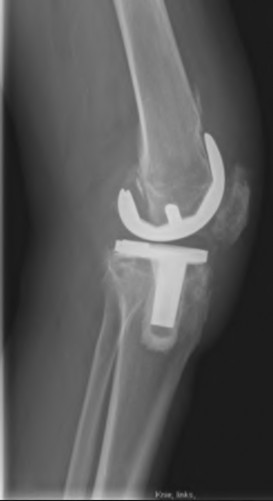

A 60-year-old male tennis player undergoes a unicompartmental knee arthroplasty (UKA) shown in Figures A and B. Which of the following statements regarding this procedure is true?

Figures A and B depict radiographs of a unicompartmental knee arthroplasty (UKA). UKA kinematics have been shown to most closely approximate native knee kinematics.

In an in vitro cadaver study, Patil et al found that TKA significantly changed knee kinematics while the unicompartmental replacement preserved normal knee kinematics.

Fisher et al performed a retrospective study comparing the short-term outcomes of small-incision unicompartmental knee arthroplasty (UKA) with standard total knee arthroplasty (TKA) in 91 consecutive patients older than 70 years. They found: 1) Blood loss was significantly more for the TKA group, as was the need for blood transfusion. 2) Patients with unicompartmental replacements had a much quicker return of function and discontinuation of pain medication. 3) While knee scores and ROM were similar preoperatively, both were better in the unicompartmental group at each postoperative time interval. 4) Narcotic use and length of hospital stay were also significantly less for the unicompartmental group. Therefore answers 2,3,4 and 5 are false.